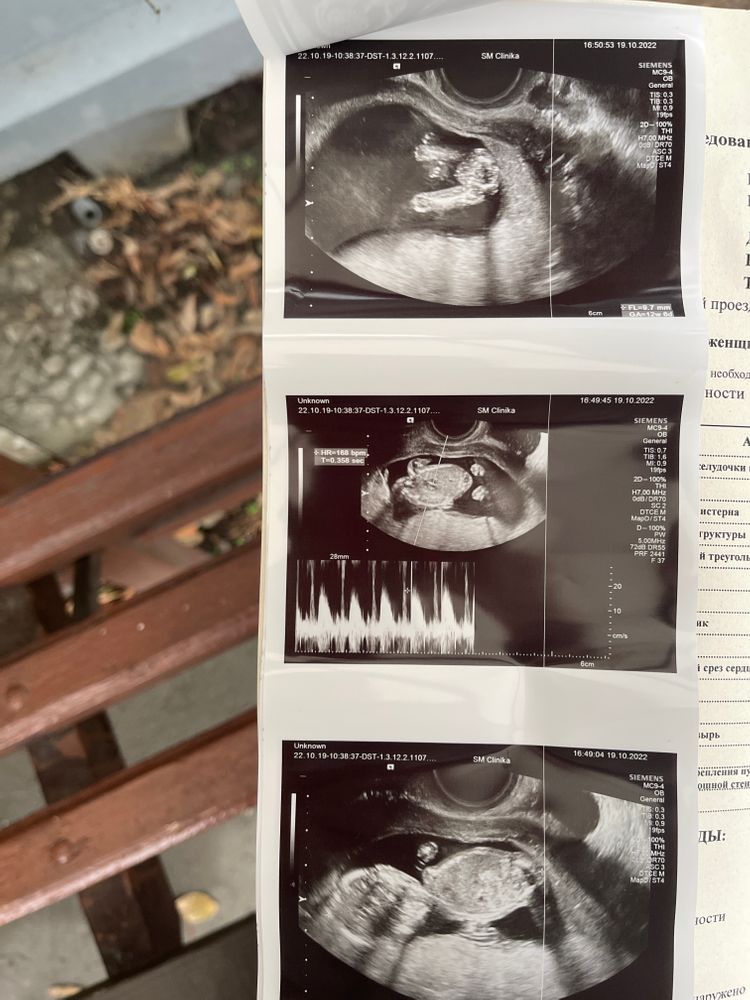

Софья, добрый день. Кого видите? Изображение

Polina Dyakova, к сожалению я по узи не понимаю🙈

Софья, сказали 95 % девочка❤️

Мне кажется девочка. Здесь столько было фоток с такого ракурса, у мальчиков между ног уже виднеется., но время покажет.

Кажется,девочка)